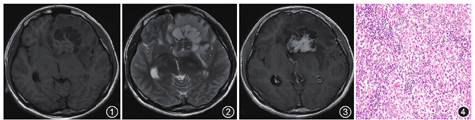

影像表现:外院CT检查示左侧额叶高低混杂密度影,界限不清。本院MRI平扫及增强:病变呈混杂信号,部分边缘模糊不清,大小约5.1 cm×4.4 cm,边缘见多发囊性信号影,呈花瓣样排列,实性部分在T1WI呈等信号(图1),T2WI呈等信号(图2),液体衰减反转恢复(FLAIR)序列呈等及稍高信号,DWI呈等信号影,病变累及胼胝体膝部及左侧基底节,并突向右侧额叶,包绕左侧脑室前角、体部的前部,周围见大片水肿,局部中线右移。增强扫描实性部分明显强化,囊性部分可见边缘强化(图3)。

手术及病理:行幕上功能区肿瘤切除术,肿瘤送病理检查:肉眼见淡褐色、实性碎组织一堆。镜下见小淋巴细胞沿纤维血管间隙浸润(图4),肿瘤细胞大小较为一致,核大,空泡状,核仁明显,大部分胞质透亮,局部嗜酸性,可见核分裂象。免疫组织化学染色:细胞增殖标记物Ki-67(阳性+70%),角化蛋白、CD117及干细胞标记物(SALL4、Oct3/4)均为阳性,波形蛋白(Vimentin)、酸性钙结合蛋白(S-100)、胶质纤维酸性蛋白(GFAP)、少突胶质细胞转录因子(Oligo-2)为阴性。病理诊断:左侧额叶生殖细胞瘤(germ cell tumor,GCT)。